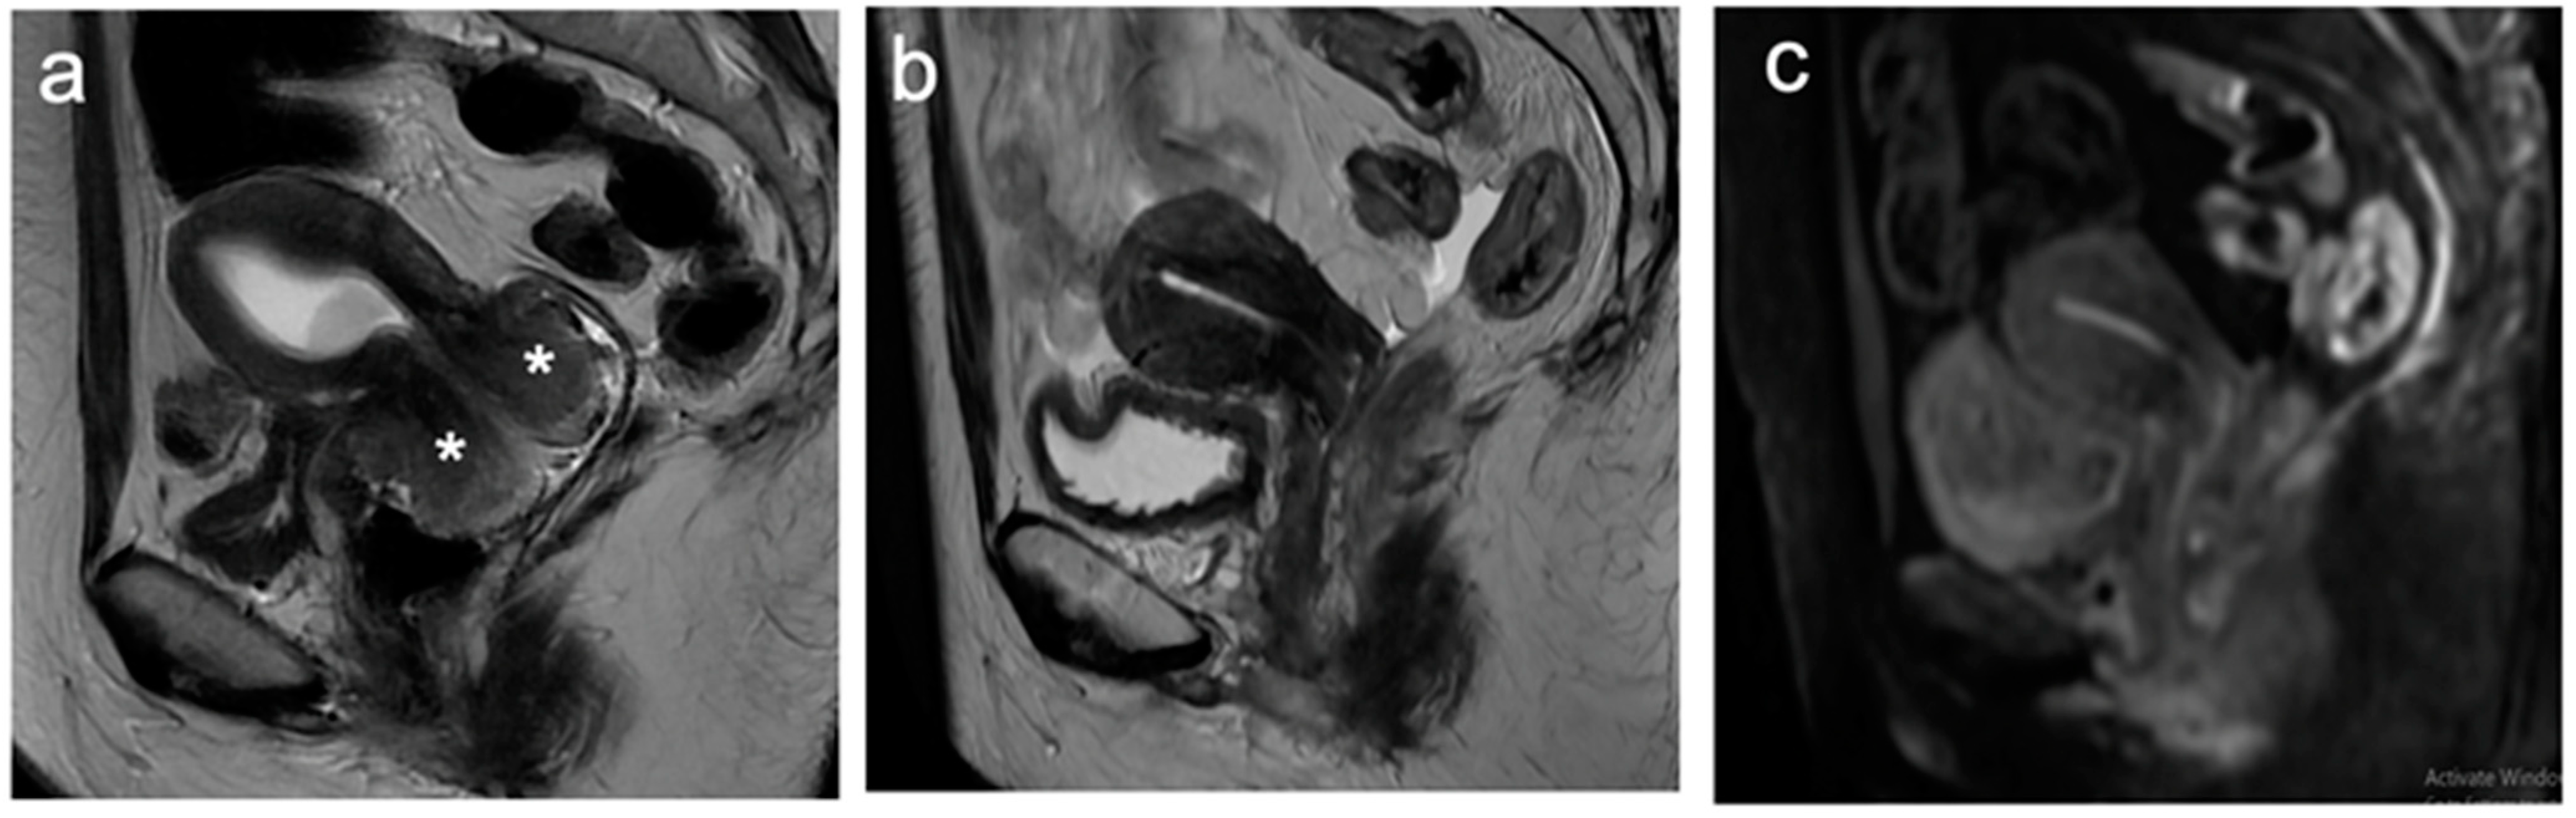

5. FIGO Stage II

- McEvoy, S.H.; Nougaret, S.; Abu-Rustum, N.R.; Vargas, H.A.; Sadowski, E.A.; Menias, C.O.; Shitano, F.; Fujii, S.; Sosa, R.E.; Escalon, J.G.; et al. Fertility-sparing for young patients with gynecologic cancer: How MRI can guide patient selection prior to conservative management. Abdom. Radiol. 2017, 42, 2488–2512, Erratum in Abdom. Radiol. 2017, 42, 2966–2973. [Google Scholar]

- Halaska, M.; Robova, H.; Pluta, M.; Rob, L. The role of trachelectomy in cervical cancer. Ecancermedicalscience 2015, 9, 506. [Google Scholar] [CrossRef]

- Rockall, A.G.; Qureshi, M.; Papadopoulou, I.; Saso, S.; Butterfield, N.; Thomassin-Naggara, I.; Farthing, A.; Smith, J.R.; Bharwani, N. Role of Imaging in Fertility-sparing Treatment of Gynecologic Malignancies. Radiographics 2016, 36, 2214–2233. [Google Scholar] [CrossRef] [PubMed]

- Moro, F.; Bonanno, G.M.; Gui, B.; Scambia, G.; Testa, A.C. Imaging modalities in fertility preservation in patients with gynecologic cancers. Int. J. Gynecol. Cancer 2021, 31, 323–331. [Google Scholar] [CrossRef] [PubMed]

- Noël, P.; Dubé, M.; Plante, M.; St-Laurent, G. Early cervical carcinoma and fertility-sparing treatment options: MR imaging as a tool in patient selection and a follow-up modality. Radiographics 2014, 34, 1099–1119. [Google Scholar] [CrossRef] [PubMed]